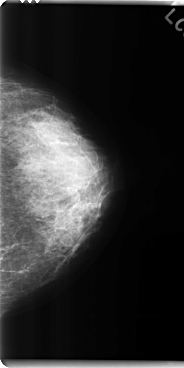

C_0284_1.LEFT_MLO

C_0284_1.LEFT_CC

LEFT_MLO LINES 4608 PIXELS_PER_LINE 2872 BITS_PER_PIXEL 12 RESOLUTION 50 NON_OVERLAY